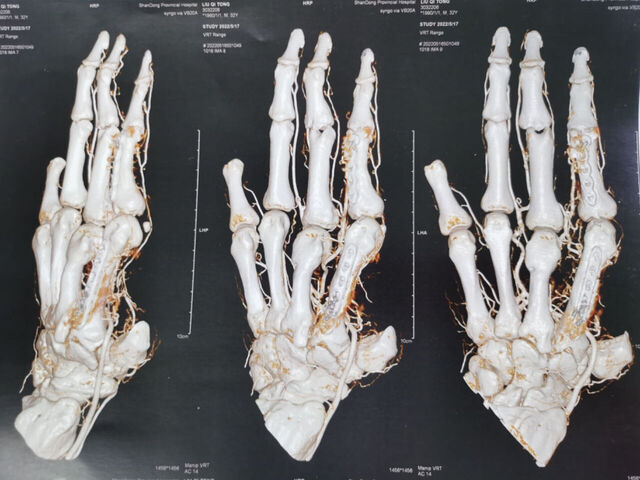

昨天的手术。

微信图片_20231008195909.jpg 微信图片_20231008195912.jpg 微信图片_20231008195906.jpg 微信图片_20231008195903.jpg 微信图片_20231008195829.jpg 微信图片_20231008195839.jpg 微信图片_20231008195836.jpg 微信图片_20231008195945.jpg 微信图片_20231008195939.jpg